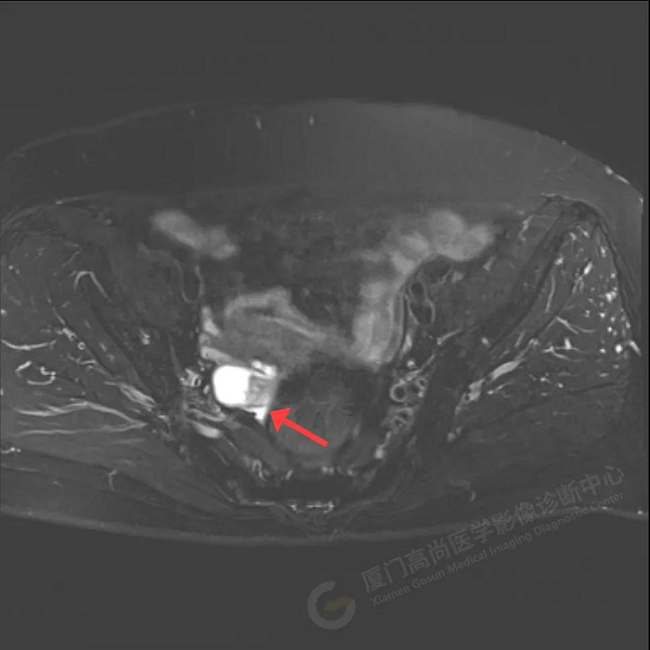

初步診斷:右側附件區(qū)囊實性占位伴腫大淋巴結,考慮卵巢來源惡性腫瘤,卵巢Ca可能性大。為進一步明確病灶良惡性、大小、是否有轉移,吳阿姨在我中心進行了PET/CT檢查。

PET/CT影像圖

診斷意見:1、右側附件區(qū)囊實性結節(jié),代謝增高,考慮為卵巢來源惡性腫瘤(囊腺癌)

2、子宮直腸陷凹內多發(fā)腫大淋巴結,代謝不同程度增高,考慮為轉移。

術后病理顯示:卵巢高級別漿液性癌2期。